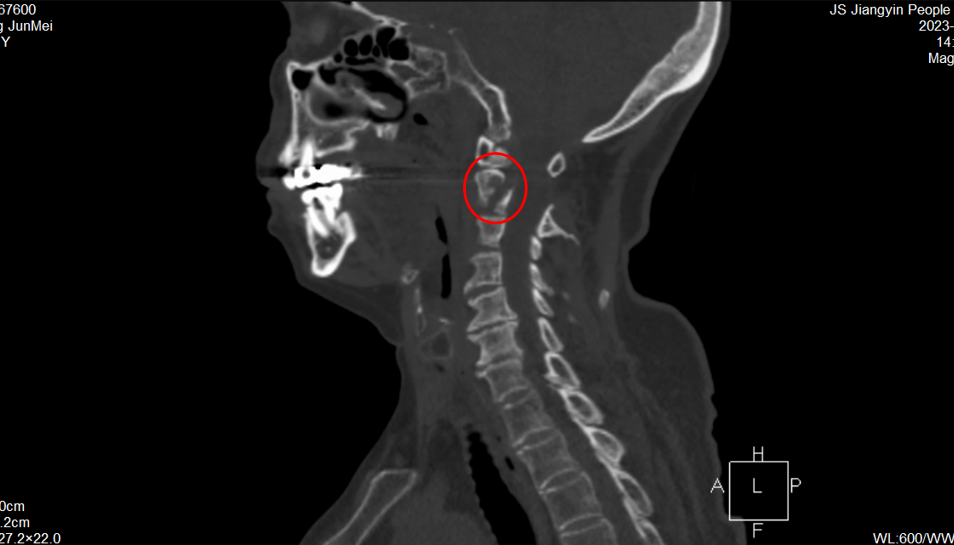

王先生術前CT

今年8月下旬,王先生因雙上肢酸痛、麻木難忍一月余才來就診。X線檢查顯示,王先生樞椎陳舊性骨折不愈合。脊柱創傷外科醫療團隊詳細評估認為,患者寰椎樞椎極度不穩定,隨時可能截癱進而危及生命,需盡快手術治療。此時,王先生毅然選擇手術,解決“折磨”了自己30余年“心頭大患”。